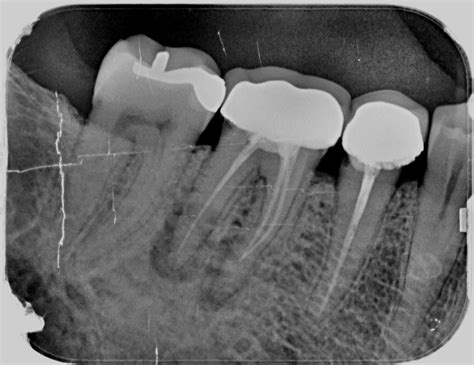

Radiografía de una Endodoncia Mal Hecha

Una de las herramientas más seguras y fiables para detectar una endodoncia fracasada es la radiografía dental. En estas imágenes se observa una lesión radiotransparente alrededor del ápice del diente, con una endodoncia bien hecha en principio, pero fracasada finalmente, y su posterior curación radiográfica tras una cirugía periapical.

Mediante una radiografía se puede observar:

- Sobreobturación: cuando el material de obturación se extiende más allá de la raíz, puede irritar los tejidos periapicales.

- Lesiones periapicales: se identifican como áreas más oscuras o radiotransparentes alrededor del ápice del diente.

- Conductos no tratados: puede que existan conductos adicionales sin tratar, los cuales aparecen como áreas radiotransparentes, ya que no han sido limpiados ni rellenados.

- Fracturas radiculares: aunque a veces son difíciles de detectar, pueden verse como líneas finas y oscuras a lo largo de la raíz.